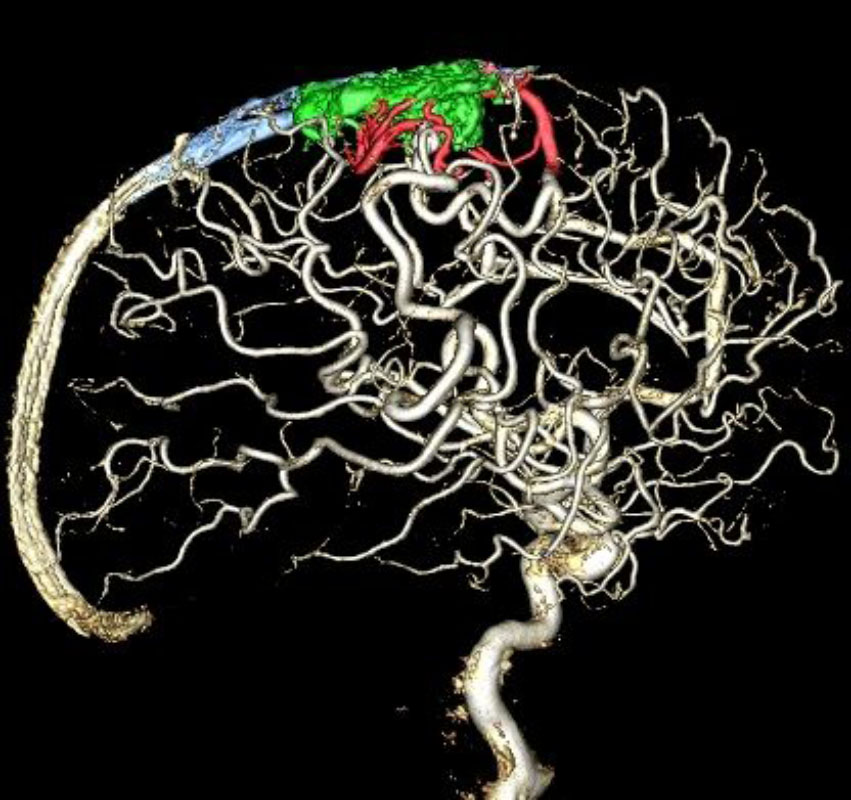

'19年5月

30代

富永/久貝

右中小脳脚 出血再発

SM 3(S1,E1,V1)

米国の病院

No.359 モニタリング

No.359 手術前

No.359 手術中

No.359 手術後

出血既往があり。2回の手術前血管内手術の後に、

Lateral transpeduncular approachにより再々出血予防を目的に

摘出手術を行う。完全摘出であることを確認した。

手術による合併症や後遺症なしで退院した。経過良好。